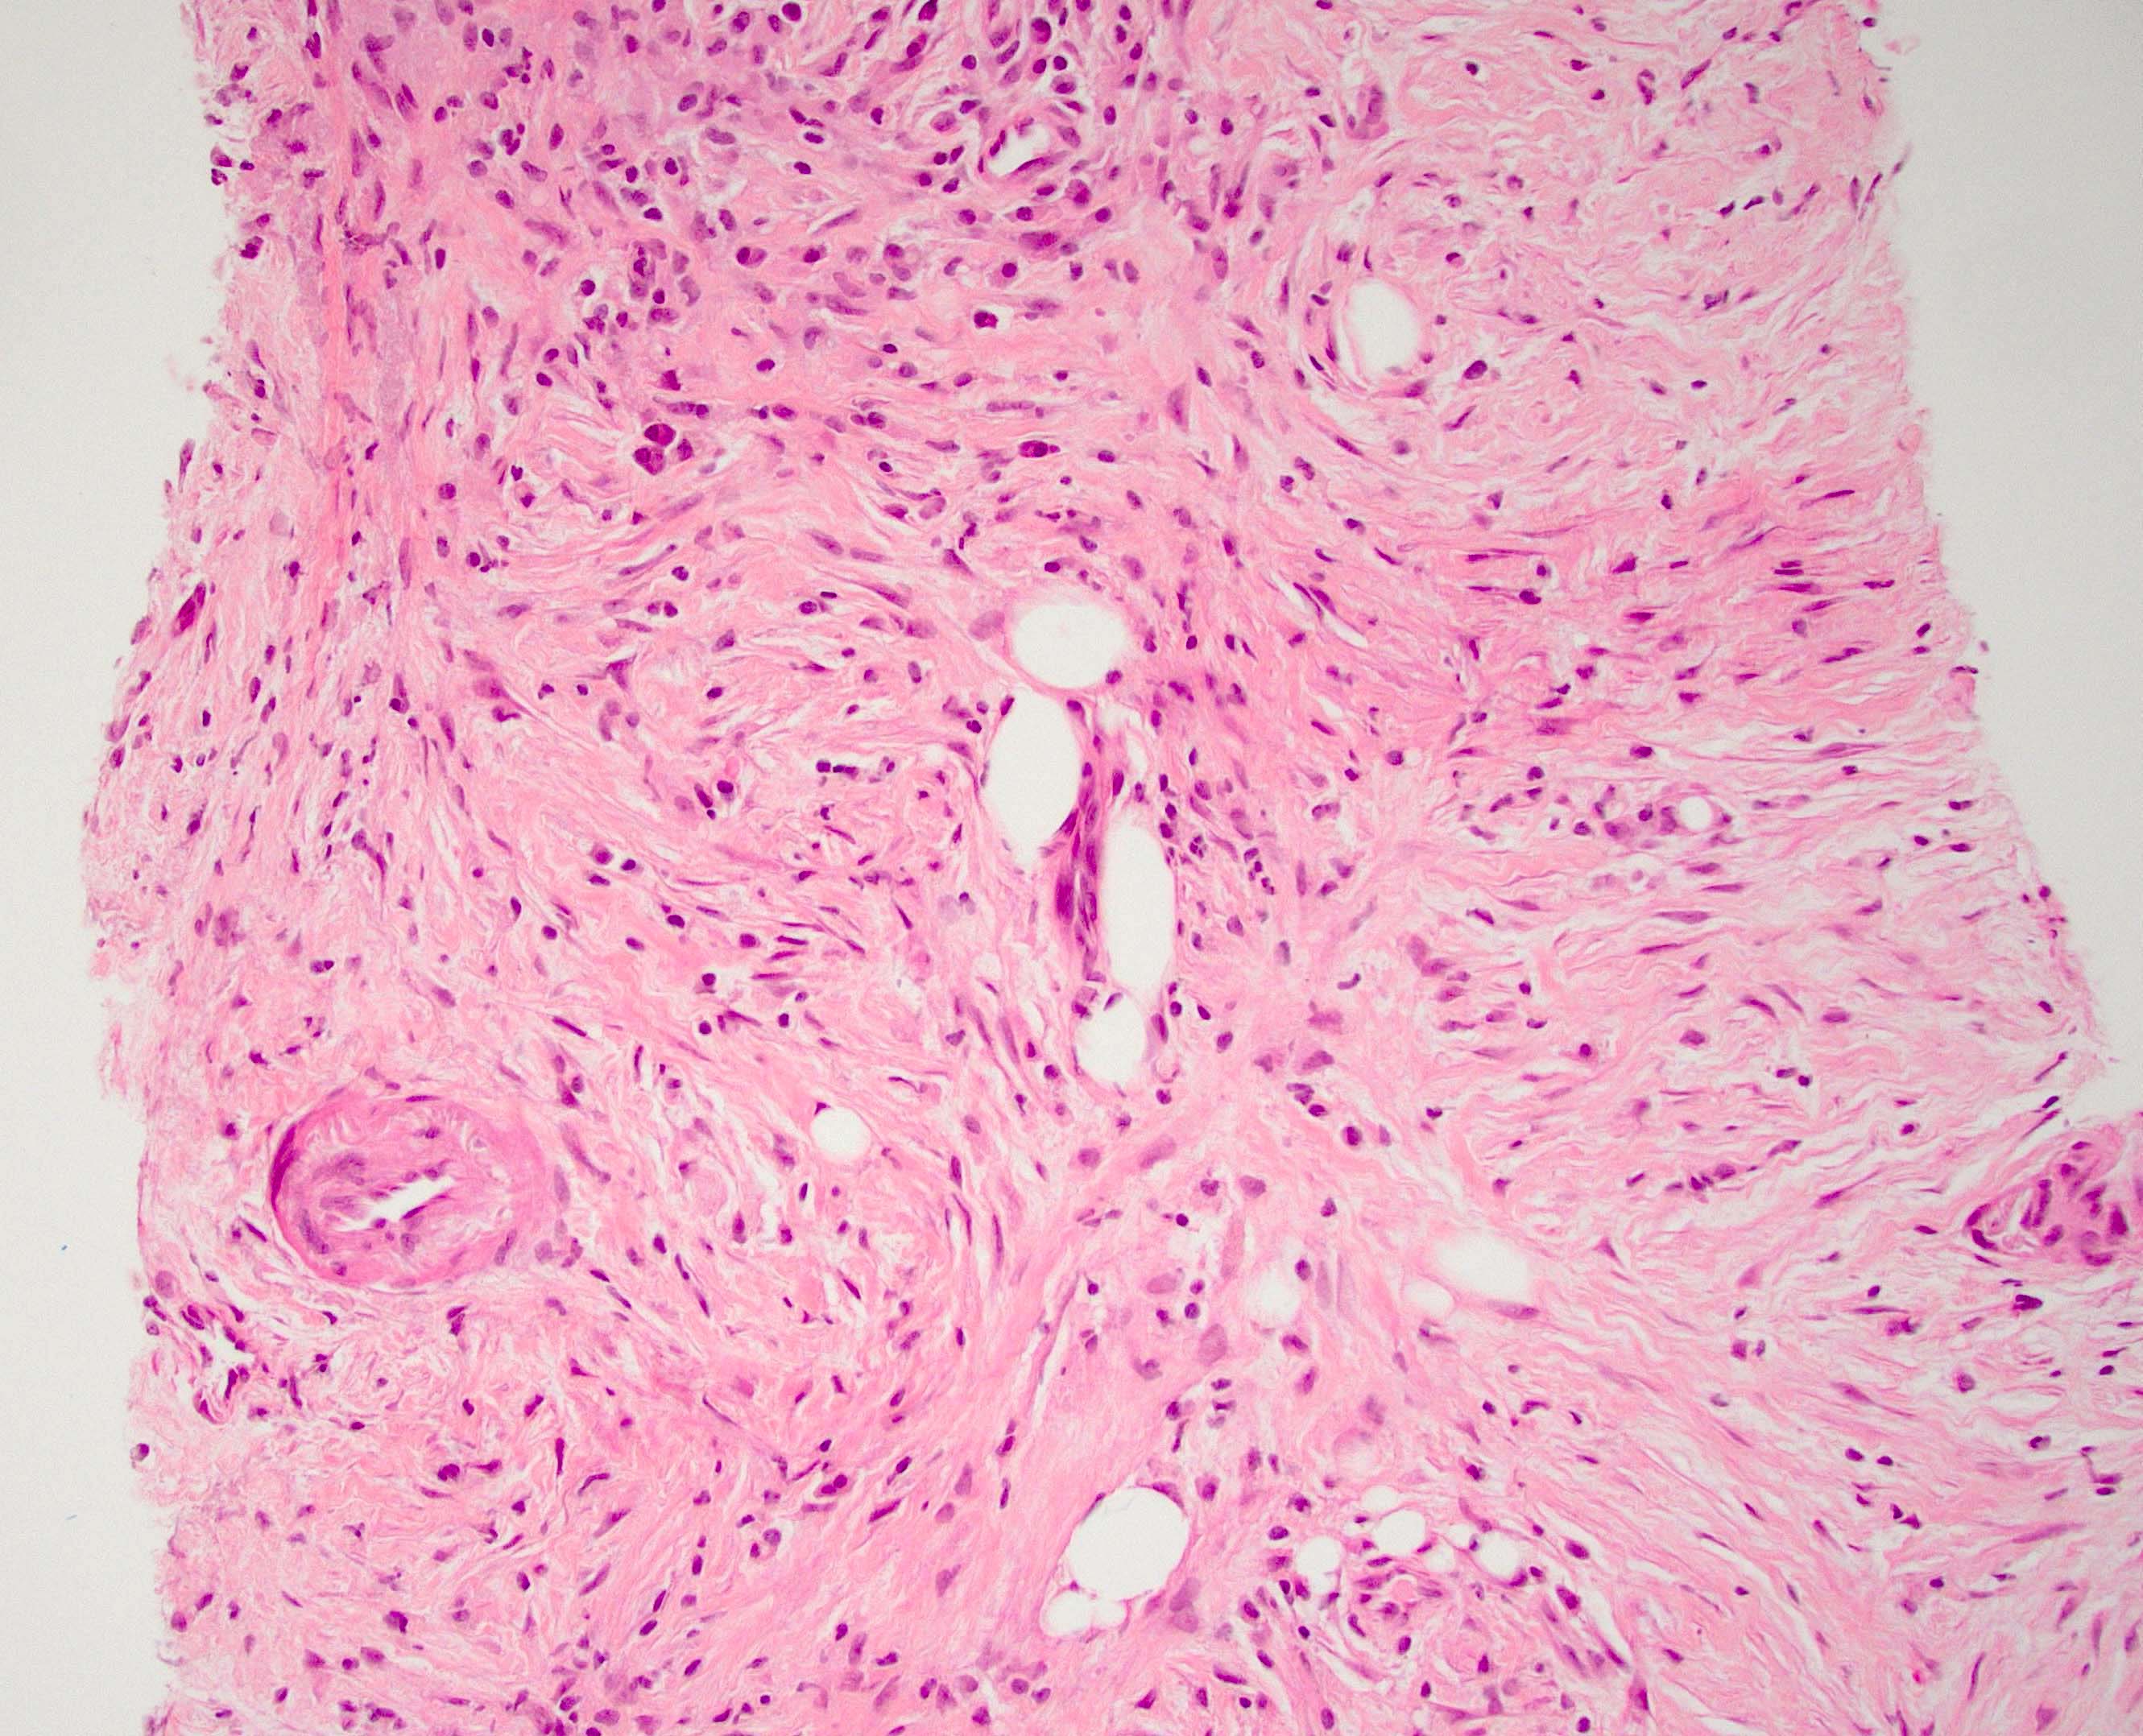

Microscopic (histologic) description

- Characteristic findings (at least 3 for level 1 criteria) (Pancreas 2011;40:352)

- Periductal lymphoplasmacytic infiltrate without granulocytic infiltration

- Obliterative phlebitis

- Storiform fibrosis

- Abundant (> 10 cells/high power field) IgG4 positive plasma cells

- Biopsy showing some but not all of the above features can be used as supportive evidence for the diagnosis of autoimmune pancreatitis (Pancreas 2011;40:352)

- Inflammation is localized within the pancreatic parenchyma and is centered around / within medium to large interlobular ducts, which causes shrinkage of the ductal lumen (Pathologica 2020;112:197)

- Inflammation can also be seen between the pancreatic parenchyma and peripancreatic adipose tissue (Pathologica 2020;112:197)

- Inflammation of the venous wall can progress to obliterative phlebitis with fibrosis of the lumen (Pathologica 2020;112:197)

- As the inflammation progresses, fibrosis becomes more diffuse, assuming a whorled or storiform pattern (Pathologica 2020;112:197)

- Perineural inflammation can also be present (Pathologica 2020;112:197)

- Involvement of the pancreatic neck margin or biliary resection margin should be clearly stated in the pathology report for therapeutic purposes (Pathologica 2020;112:197)

Microscopic (histologic) images